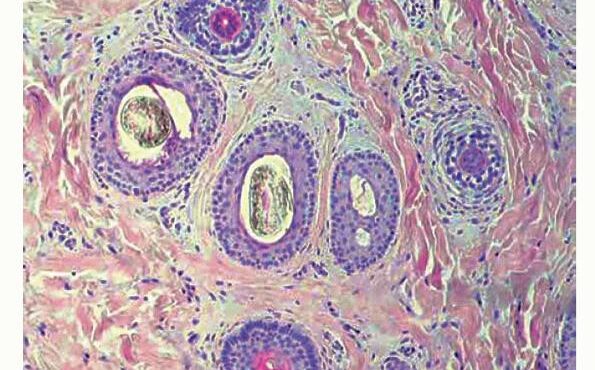

Read MoreFibrous papule (angiofibroma) = حطاطة تليفية =ليفوم وعائي OLYMPUS DIGITAL CAMERA OLYMPUS DIGITAL CAMERA FIBROUS PAPULE Currently, there is some disagreement as to whether fibrous papule represents a neoplastic process or a hamartoma.Fibrous papule (perifollicular fibroma) presents mainly as a solitary papule or as several dome-shaped, skin-colored, pigmented, or reddish lesions situated on the face, […]